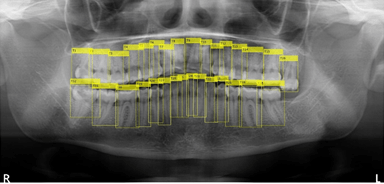

人工知能画像解析による歯科医院向け パノラマレントゲン画像からの歯牙全自動認識法の確立

株式会社ナルコーム(本社:長野県佐久市、代表取締役:猪俣 吾郎)と公立大学法人兵庫県立大学 大学院工学研究科(所在地:兵庫県姫路市、小橋 昌司教授 先端医工学研究センター長)は、AI技術を用いた歯科パノラマレントゲン画像の歯牙認識システム(以後 本システム)を共同で研究開発しました。

従来、歯科医院ではパノラマレントゲンの撮影後、歯科医師が目視で患者の歯牙情報をカルテや患者管理ソフトに入力し、診査・診断等を行っていました。本システムは、パノラマレントゲンの画像データから歯牙情報の有無をAI技術で自動解析し、また解析後の歯牙情報をアウトプットするものです。

本技術(特許出願中 出願番号:特願2020-132917)は、Springer Nature社のScientific Reportsに2020年11月6日付けで掲載された論文「Optimization Technique Combined with Deep Learning Method for Teeth Recognition in Dental Panoramic Radiographs」に基づきます。